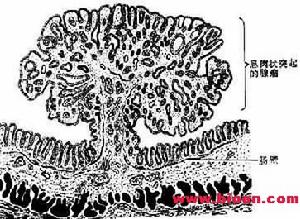

結腸直腸腺瘤① 脆性:在檢查時,以窺器或器械觸及時極易出血者,多為惡性息肉。反之則為良性。

② 潰瘍:息肉一般情況下無潰瘍,當惡變時,即可形成潰瘍,特別是帶蒂的息肉一般不會引起潰瘍,一旦發生潰瘍,則表明其有惡性改變。

③ 活動性:堅實牢固、無蒂的息肉易惡變;而帶蒂具有活動性的則惡變相對較低。

④ 外形:有分葉的息肉易惡變,光滑圓潤的則少。

⑤ 基底:息肉基底大,頭小者極易惡變。

⑥ 類型:有蒂的多是管狀腺瘤,相對癌變率較低。

⑦ 大小:息肉增大或息肉較大的易惡變,息肉無明顯增大的,則較少惡變。